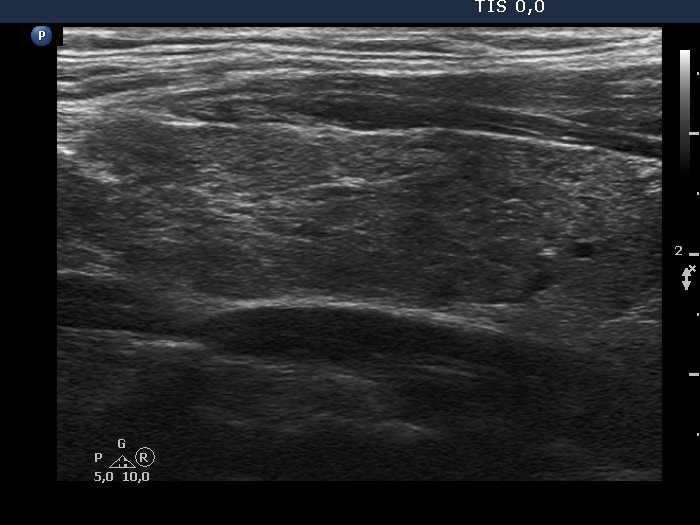

Consecutively operated patients with autoimmune thyroid disease - case 67 (conp 084) (ultrasonographic picture 5)

Left lobe, longitudinal scan. This section shows the usual pattern of Hashimoto's thyroiditis.